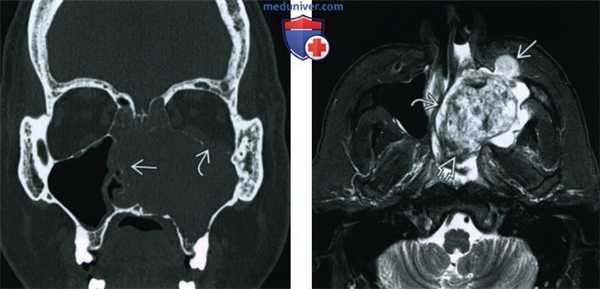

(Слева) При корональной КТ пазух у пациента 31 года с носовыми кровотечениями и ОГПН определяется снижение пневматизации левой верхнечелюстной пазухи за счет мягкотканного содержимого и ее вздутие. Определяется также резорбция дна левой орбиты с легким пролабированием ОГПН в орбиту, и полная эрозия внутренней стенки и перегородки.

(Справа) При аксиальной МРТ Т2 FS у этого же пациента визуализируется неоднородное объемное образование в левой верхнечелюстной пазухе с фокальным нарушением целостности передней стенки и полной эрозией внутренней стенки с распространением образования в полость носа и носоглотку.

(Слева) При аксиальной МРТ Т1 у этого же пациента визуализируется изоинтенсивное образование, приводящее к вздутию левой верхнечелюстной пазухи. Разрозненные зоны гиперинтенсивного (Т1) сигнала свидетельствуют о недавнем кровоизлиянии.

(Справа) При аксиальной МРТ Т1 С+ FS у этого же пациента в левой верхнечелюстной пазухе и полости носа визуализируется крупная экспансивная ОГПН.